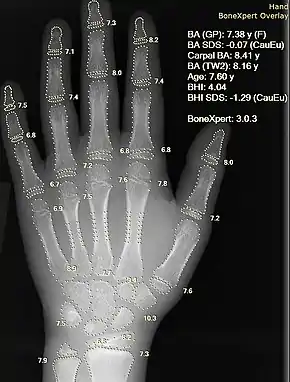

Medical image computing and imaging informatics

Imaging informatics and medical image computing develops computational and mathematical methods for solving problems pertaining to medical images and their use for biomedical research and clinical care. Those fields aims to extract clinically relevant information or knowledge from medical images and computational analysis of the images. The methods can be grouped into several broad categories: image segmentation, image registration, image-based physiological modeling, and others.